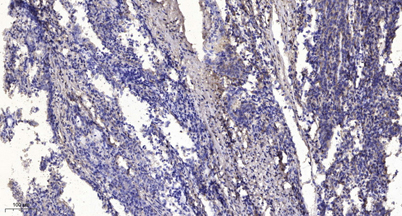

Immunohistochemical analysis of paraffin-embedded human Gastric adenocarcinoma. 1, Antibody was diluted at 1:200(4° overnight). 2, Tris-EDTA,pH9.0 was used for antigen retrieval. 3,Secondary antibody was diluted at 1:200(room temperature, 45min).